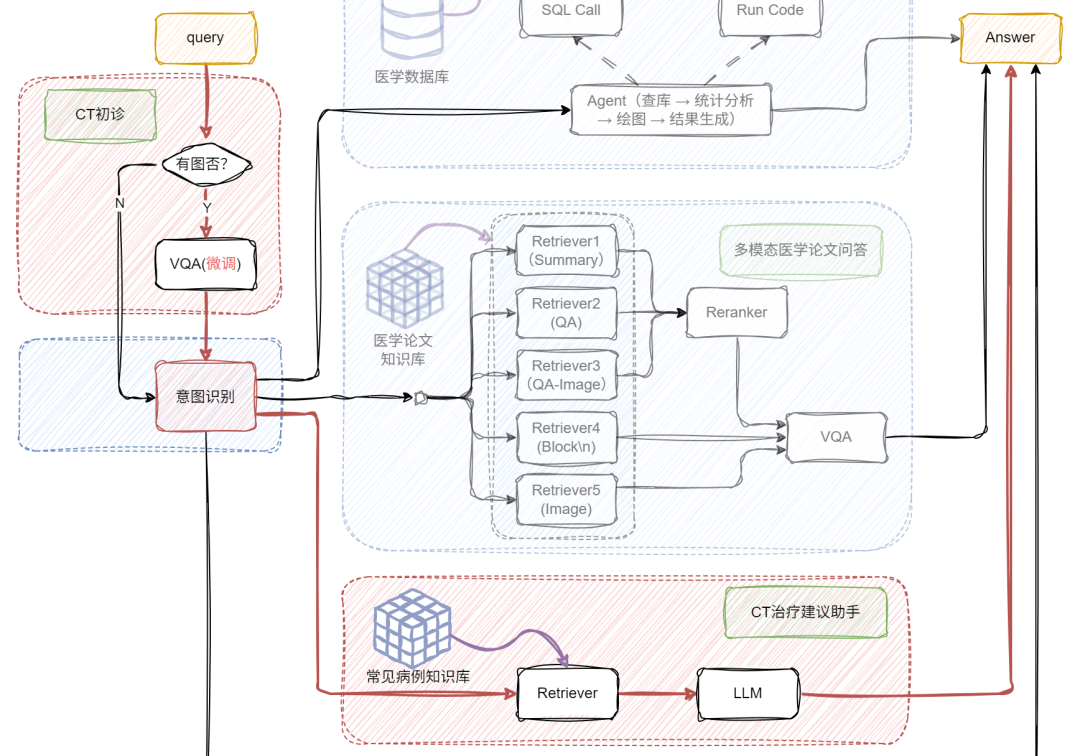

下图和视频效果是我们今天的目标!涉及多路召回多模态RAG、多模态问答、Chat-BI、Agent、LLM微调、多模态模型微调等等。让我们开始吧!

通过前面的探索,我们已经了解了朴素 RAG 如何让大模型具备“查资料再回答”的基础能力,也见证了多模态 RAG 通过图文融合实现的“感官升级”。但当实际应用场景涉及“医院年度病例统计分析”、“科研文献数据可视化呈现”等需求时,单纯的多模态处理仍显不足 —— 这类场景既需要解析医学影像、病历文本等非结构化数据,又要对接数据库完成指标计算、图表生成等 BI任务。

如何让 RAG 系统同时驾驭多模态理解与结构化数据分析?接下来要展开的多模态 + BI复杂架构实战,正是为解决这类“既要又要”的高阶需求而生,我们将在朴素 RAG 基础上层层叠加关键模块,最终打造出能同时处理影像诊断、数据统计、图表生成的全能型 AI 助手!

首先登场的是

VQA 模块(Visual Question Answering)

当用户提问中包含图片时,系统会自动触发 VQA,对图像进行结构化信息提取,挖掘上下文关键内容;若没有图像,就跳过这步,直接进入文本处理环节,效率UPUP!

接下来,系统通过意图识别模块,将不同类型的问题智能分流:

📌论文问答? 走传统 RAG 路线!向量检索+大模型生成,精准提取相关文献内容。

📌统计问答? 开启 SQL 模式!从提问中抽取结构化信息(如指标、维度、过滤条件),自动生成 SQL 查询,查询结果再由大模型“翻译”成自然语言,一目了然!

这部分我们聚焦在医学论文问答场景,结合文本+图像的多模态输入,构建一个更智能的 RAG 系统,并支持返回可视化图表。整体框架的细节如下:

首先,我们将PDF解析成文本和图像;文本部分我们可以通过\n切分、LLM(总结)和 LLM(QA)等方式构造不同的block文本节点;图像部分我们通过多模态大模型构建相应的QA文本节点qapair_img和图像根节点;接下来,我们将所有节点统一编码入库,并通过多路召回机制进行语义匹配与内容检索;在召回阶段之后,引入重排序机制,进一步优化检索结果的相关性与准确性;最后,系统会将用户的查询(query)与召回得到的上下文(context)内容一并输入至多模态大模型,由其生成最终答案。整体代码实现如下:

在已有的多模态论文问答系统基础上,我们进一步集成了统计分析机制,让系统不仅能“看图识意”,还能“分析数据、输出结论”。这样一来,系统就不仅仅是一个问答助手,更像是一个拥有知识库+分析大脑+视觉理解力的超级 AI 学者 。主要实现代码如下:

def build_paper_assistant():llm = OnlineChatModule(source='qwen', stream=False)vqa = lazyllm.OnlineChatModule(source="sensenova",\model="SenseNova-V6-Turbo").prompt(lazyllm.ChatPrompter(gen_prompt))with pipeline() as ppl:ppl.ifvqa = lazyllm.ifs(lambda x: x.startswith('<lazyllm-query>'),vqa, lambda x:x)with IntentClassifier(llm) as ppl.ic:ppl.ic.case["论文问答", paper_ppl]ppl.ic.case["统计问答", sql_ppl]return ppl

6 多模态 + BI + 医疗落地:

基于前面多模态与 BI 能力的深度融合实践,我们进一步将 RAG 系统向医疗垂直场景做了进阶升级 —— 如今这套架构不仅能处理常规的文本问诊,更能通过 VQA 模块与医学知识库的联动,实现 CT 影像解析与智能诊断辅助的核心能力,打通了从临床咨询到辅助决策的全流程服务闭环。下面就带大家看看这套融合多模态理解、数据统计与专业知识的医疗 RAG 系统是如何落地的!

def build_paper_assistant():llm = OnlineChatModule(source='qwen', stream=False)with pipeline() as ppl:ppl.ifvqa = lazyllm.ifs(lambda x: x.startswith('<lazyllm-query>'),vqa_ppl, lambda x:x)with IntentClassifier(llm) as ppl.ic:ppl.ic.case["论文问答", paper_ppl]ppl.ic.case["统计问答", sql_ppl]ppl.ic.case["普通医疗问诊", inquiry_ppl]ppl.ic.case["CT医疗问诊", ct_ppl]return ppl